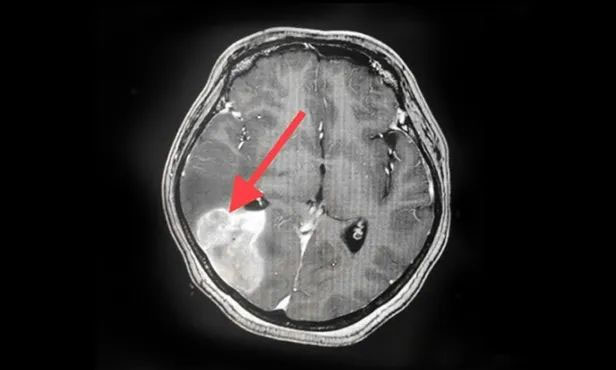

▲ 经复查,病灶较前明显缩小

按照肿瘤复查的标准,复查影像显示王女士颅内病灶相较于来院时明显缩小。家属为此特意向陈琦主任致谢,并对医院的治疗和服务表达了充分肯定。